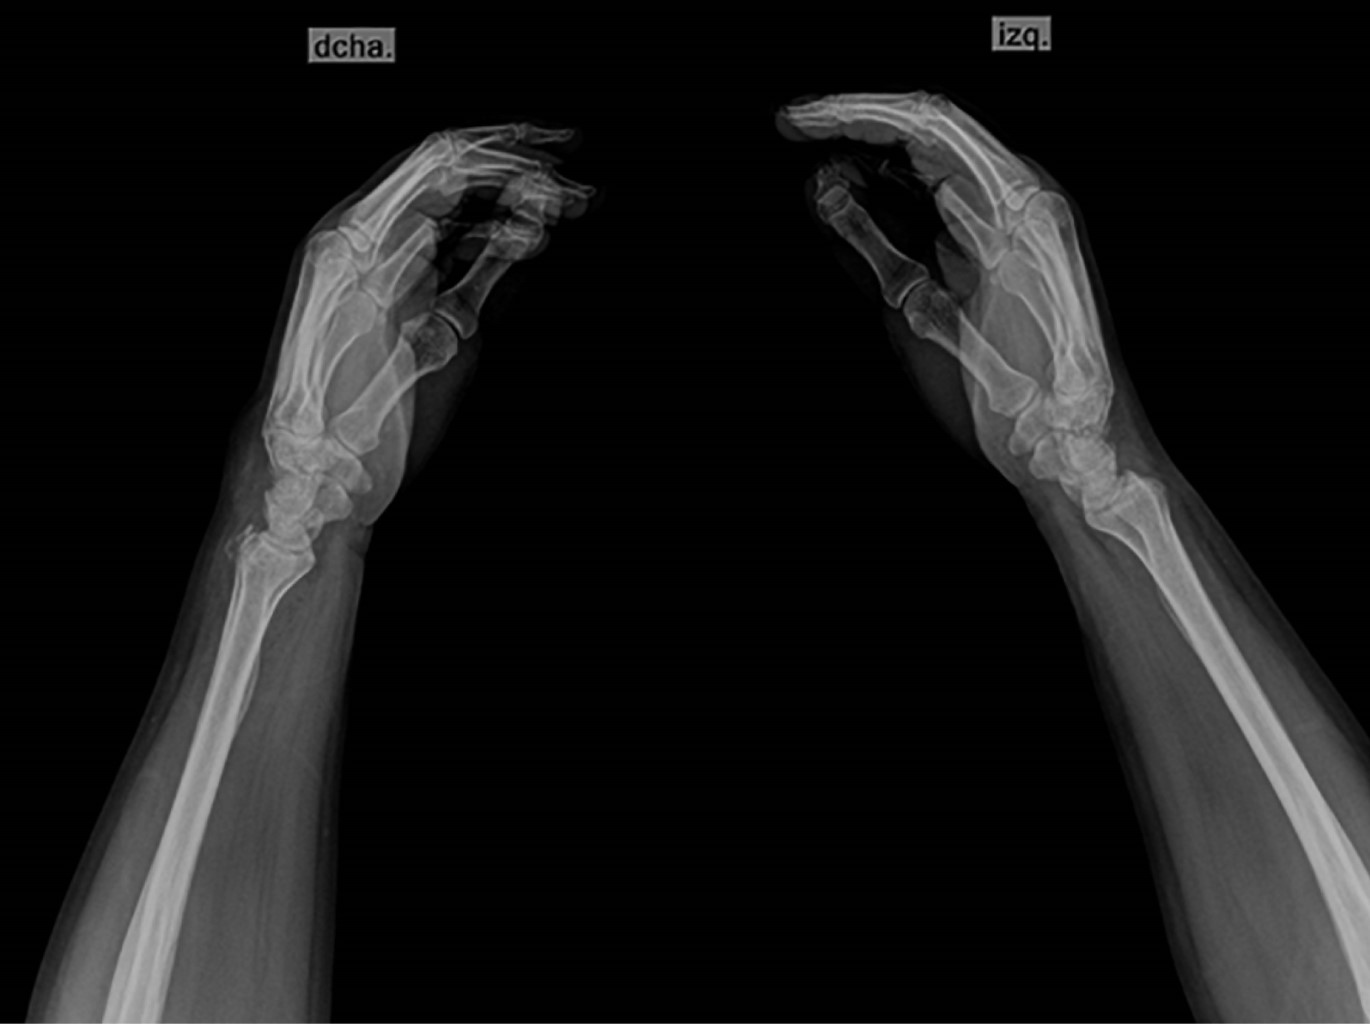

A su ingreso se evalúa por el Servicio de Ortopedia del hospital y se solicitan estudios complementarios por sospecha de fractura. En proyecciones dorsopalmar (Figura 1) y lateral (Figura 2) de ambas manos (con dificultad para su adquisición debido a la limitación de la movilidad por trauma reciente) se evidencia trazo de fractura de la apófisis estiloides de ambas muñecas y de la faceta articular del radio distal bilateral. De forma incidental, se observa pulgar trifalángico bilateral, sin referir sintomatología a este nivel previo al evento traumático.

Figura 1